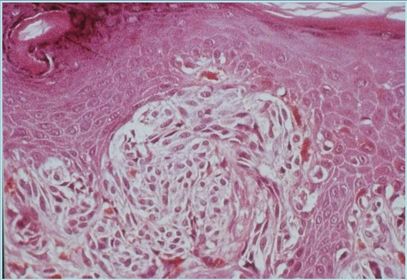

Diagnóstico e alterações CBC Células basalóides atípicas dispostas em paliçada.

Diagnóstico e Alterações CEC Proliferação de células escamosas atípicas formando grupos, perolas córneas.